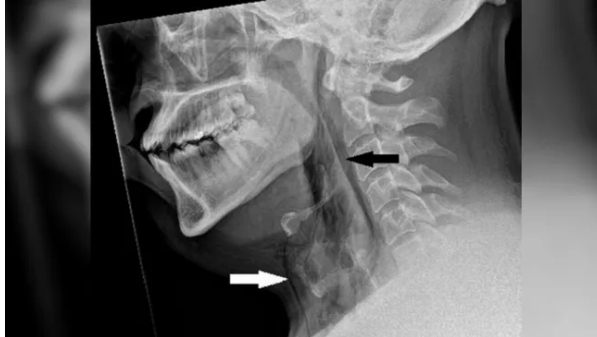

이 남성은 숨을 쉬거나 음식을 삼키거나 말하는 데 아무런 문제가 없었다. 의료진은 그의 목을 검사하면서 희미하게 딱딱거리는 소리를 들었다. 엑스레이를 찍어보니 공기가 피부 아래 조직에 갇힌 상태인 외과적 폐기종의 징후가 있었다.

CT 스캔 결과 이 환자는 목의 세 번째와 네 번째 뼈 사이가 찢어져 있었다. 공기가 목의 조직과 폐 사이 공간으로 빠져나갈 수 있었다. 구멍 크기는 가로 세로 약 2mm 정도였다.